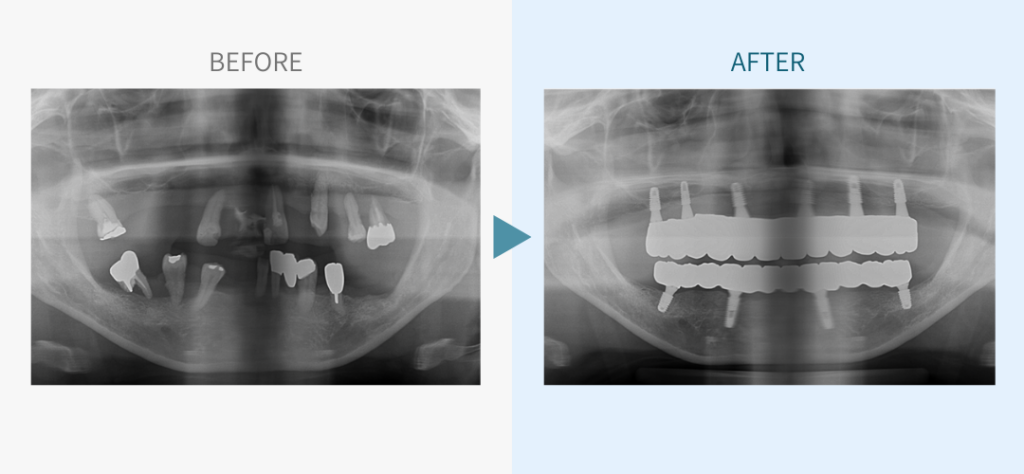

デンタルチームジャパンでは、サイナスリフト(上顎洞底挙上術)や骨造成など、他院で「骨が足りない」と断られた難症例にも対応しています。

こちらではその一部の症例についてご紹介します。